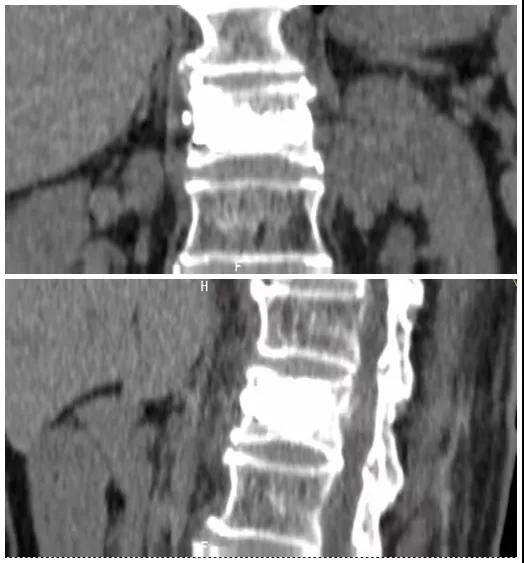

術(shù)后復(fù)查CT可見骨水泥彌散充分

經(jīng)術(shù)前分析詳細(xì)評(píng)估,由骨科副主任張宏宇及科室團(tuán)隊(duì)順利為患者進(jìn)行了經(jīng)皮穿刺椎體成形術(shù),術(shù)后患者疼痛明顯減輕。同時(shí),科室團(tuán)隊(duì)還為她制定了科學(xué)的抗骨質(zhì)疏松治療,目前患者已康復(fù)出院。